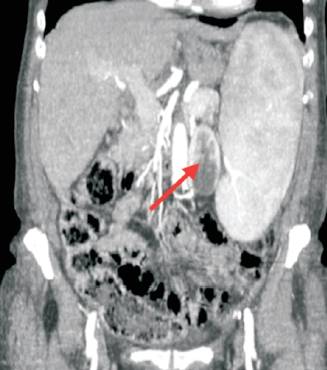

Se realizó tomografía tóraco-abdómino-pélvica que informó: esplenomegalia de densidad homogénea de 20 cm de longitud. Riñón izquierdo desplazado medialmente por la esplenomegalia. No se evidenciaron adenomegalias (figura 1).

Figura 1: Tomografía abdominal de abdomen y pelvis. Se aprecia el bazo extendido desde la cúpula diafragmática izquierda hasta el estrecho superior de la pelvis, desplazando el riñón izquierdo hacia la línea media (flecha roja).